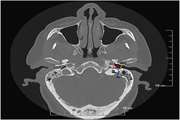

• تشخیص تومور: توسعه الگوریتم‌هایی برای تشخیص خودکار انواع تومورها در تصاویر رادیولوژی (مانند سی‌تی اسکن، ام‌آر‌آی و پت اسکن).

• تشخیص بیماری‌های قلبی-عروقی: تشخیص زودهنگام بیماری‌های قلبی-عروقی مانند آنوریسم آئورت و تنگی عروق کرونر.